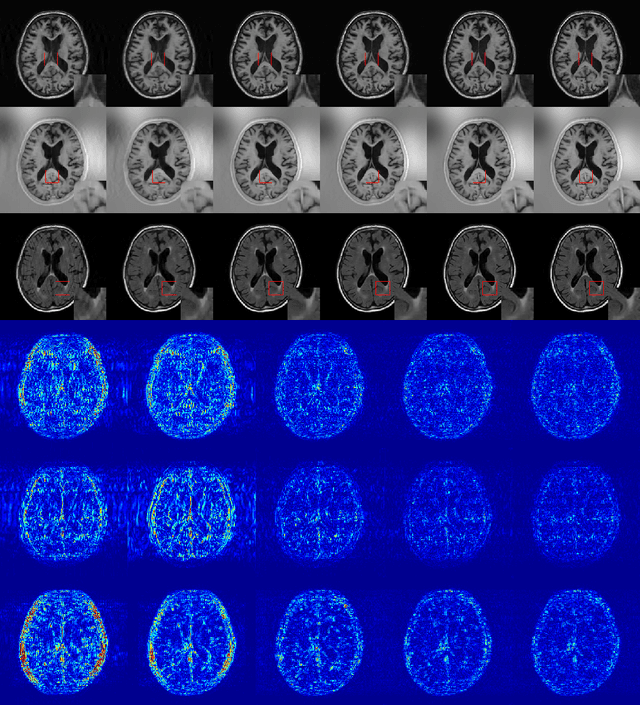

Abstract:In multi-contrast magnetic resonance imaging (MRI), compressed sensing theory can accelerate imaging by sampling fewer measurements within each contrast. The conventional optimization-based models suffer several limitations: strict assumption of shared sparse support, time-consuming optimization and "shallow" models with difficulties in encoding the rich patterns hiding in massive MRI data. In this paper, we propose the first deep learning model for multi-contrast MRI reconstruction. We achieve information sharing through feature sharing units, which significantly reduces the number of parameters. The feature sharing unit is combined with a data fidelity unit to comprise an inference block. These inference blocks are cascaded with dense connections, which allows for information transmission across different depths of the network efficiently. Our extensive experiments on various multi-contrast MRI datasets show that proposed model outperforms both state-of-the-art single-contrast and multi-contrast MRI methods in accuracy and efficiency. We show the improved reconstruction quality can bring great benefits for the later medical image analysis stage. Furthermore, the robustness of the proposed model to the non-registration environment shows its potential in real MRI applications.